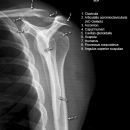

Schulter nach Morrison oder Outlet View

Indikation

v.a. Impingementsyndrom: Beurteilung des Akromions, des AC-Gelenks, evtl. hilfreich zur Diagnostik von Luxationen

Beurteilungskriterien

- Impingementsyndrom (2): Neigungswinkel des Akromions -> Je gebogener bzw. hakenförmiger desto höher ist die Wahrscheinlichkeit. Radiologische Befunde: Zystenbildung im Bereich des Tuberculum majus? Subchondrale Sklerosierung am Tuberculum majus oder subacromiale Osteophytenbildung? Verkalkungen im Verlauf der Supraspinatussehne?

- subacrominalen Raumes: normalerweise 1 - 1,5 cm, < 10 mm -> wahrscheinlich, < 6 mm -> sicher pathologisch